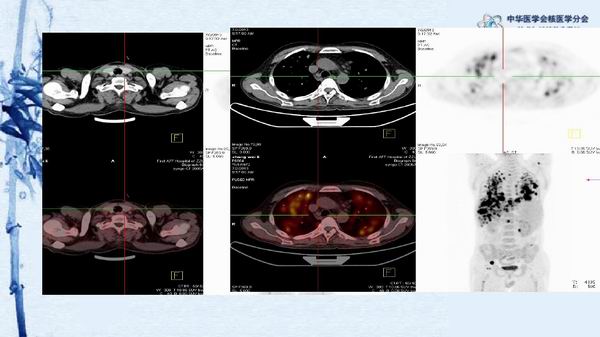

病例49:PET-CT显像诊断淋巴瘤相关噬血细胞综合征一例-【CSNM继教学组】程兵 郑州大学第一附属医院